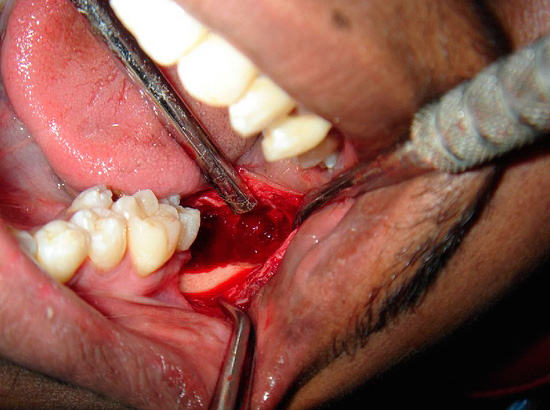

Ao remover o dente do siso, o cirurgião-dentista é frequentemente forçado a recorrer a vários truques e pode usar uma variedade de ferramentas.Muitas vezes, é impossível conviver com uma pinça, para não se surpreender e não se assustar se o médico começar literalmente a cortar seu dente em pedaços ou agarrar o cinzel e começar a bater nele ...

Infelizmente, mesmo depois que o dente do siso inferior já foi removido, as consequências da cirurgia experiente ainda podem ser sentidas no futuro - no entanto, uma grande superfície da ferida com tecidos rasgados em torno dele muitas vezes permanece na cavidade oral. Os problemas típicos que você pode encontrar ao mesmo tempo são sangramentos graves do orifício, aumento gradual da dor, inchaço da bochecha e gengivas, inflamação e supuração das paredes do orifício (alveolite) e outros.

Muitas pessoas sabem por experiência própria quanto tempo às vezes removem o dente do siso e que paleta de sensações após uma intervenção dessas aguarda em um futuro muito próximo. Na Internet, você pode encontrar um grande número de avaliações que mostram uma imagem bastante assustadora do próprio procedimento de remoção e não menos terrível depois dele.